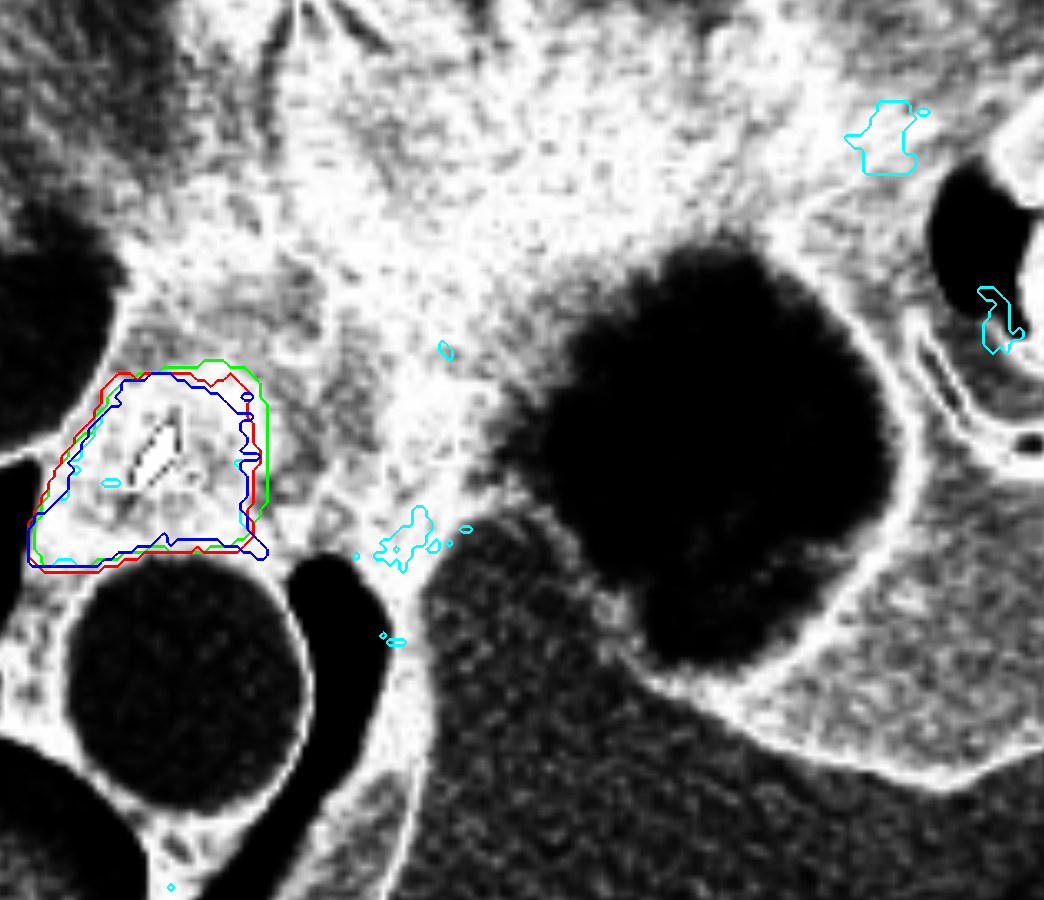

Visual results of our algorithm compared to the reference contour for 6 cases in axial and sagittal view are depicted in Fig. 5. From the sagittal views it can be observed that manual contours are not as smooth as the automatic contours, which could be due to the breathing artifacts. The use of convolutions and post-processing in 3D aids at processing information of the 3D context through several slices, which is reflected in the smoother automatic contours shown in these images. On the other hand, from the axial views we can realize that, despite of the similarity with respect to neighboring tissues, and heterogeneity of the inner region of the esophagus, our automatic system provides contours that are comparable with the reference standard.

Refer to caption a) clinical case 09 sagittal view Refer to caption b) clinical case 13 sagittal view Refer to caption c) clinical case 20 sagittal view

Refer to caption d) clinical case 09 axial view Refer to caption e) clinical case 13 axial view Refer to caption f) clinical case 20 axial view

Refer to caption g) public case 01 sagittal view Refer to caption h) public case 12 sagittal view Refer to caption i) public case 24 sagittal view

Refer to caption j) public case 01 axial view Refer to caption k) public case 12 axial view Refer to caption l) public case 24 axial view

Figure 5: Contouring results for 6 cases in different views. The green line indicates the reference standard, the red line depicts the contour generated by the proposed algorithm.